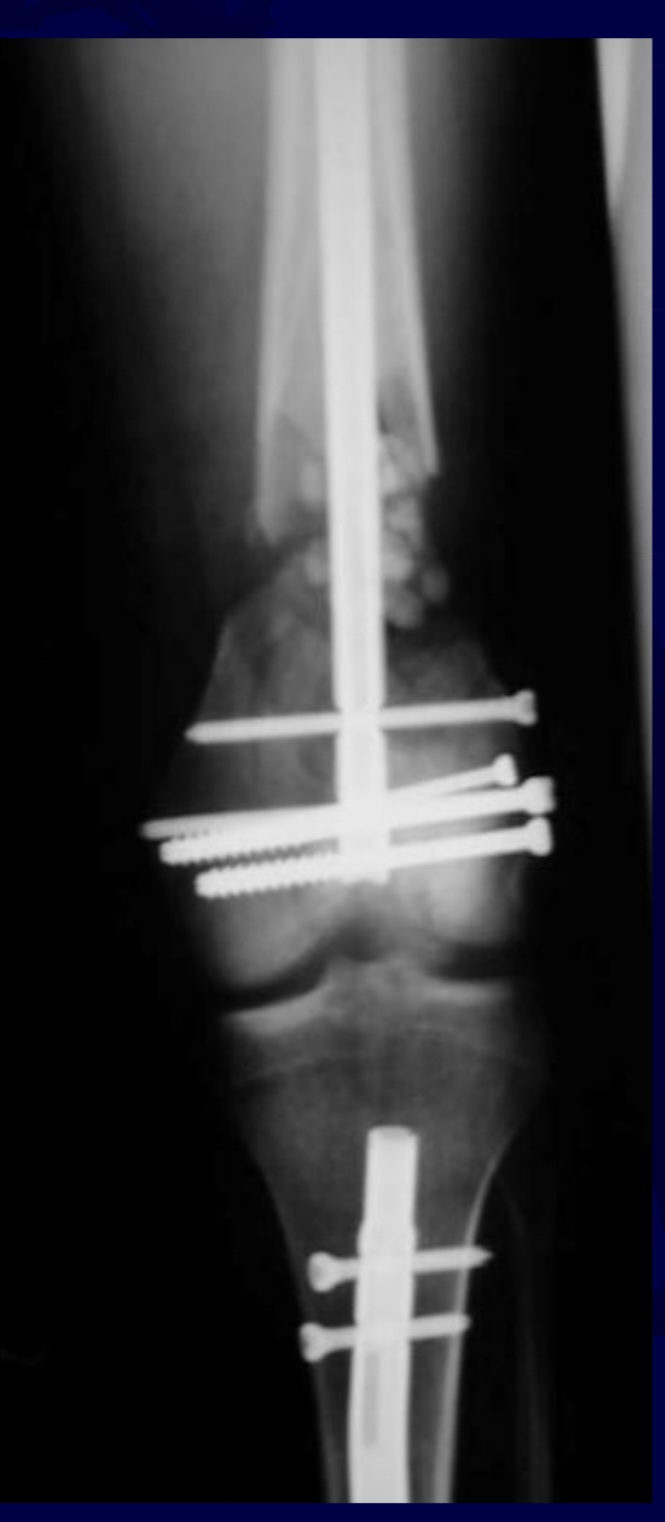

Management of Open Shaft of Tibial Fracture

Open Fractures of Tibia Diaphysis

Obtain AP and Lateral radigraphs

continue ex-fixator or remove the ex-fixator , back slab and convert to IMIL after few. weeks when pin tracts heal